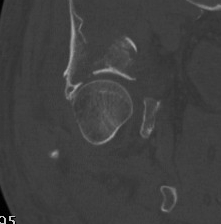

CT

Configuration

1-2 mm sections

CT reconstruction

- remove head to view acetabulum

- beware volume averaging

- used to guide surgery

Diagnose

Loose bodies

Femoral head fractures

Subtle subluxation

Articular steps

Roof arc measurement

1. Posterior Wall

- often associated with posterior dislocation

- may be in one or many pieces

- may have marginal impaction fracture